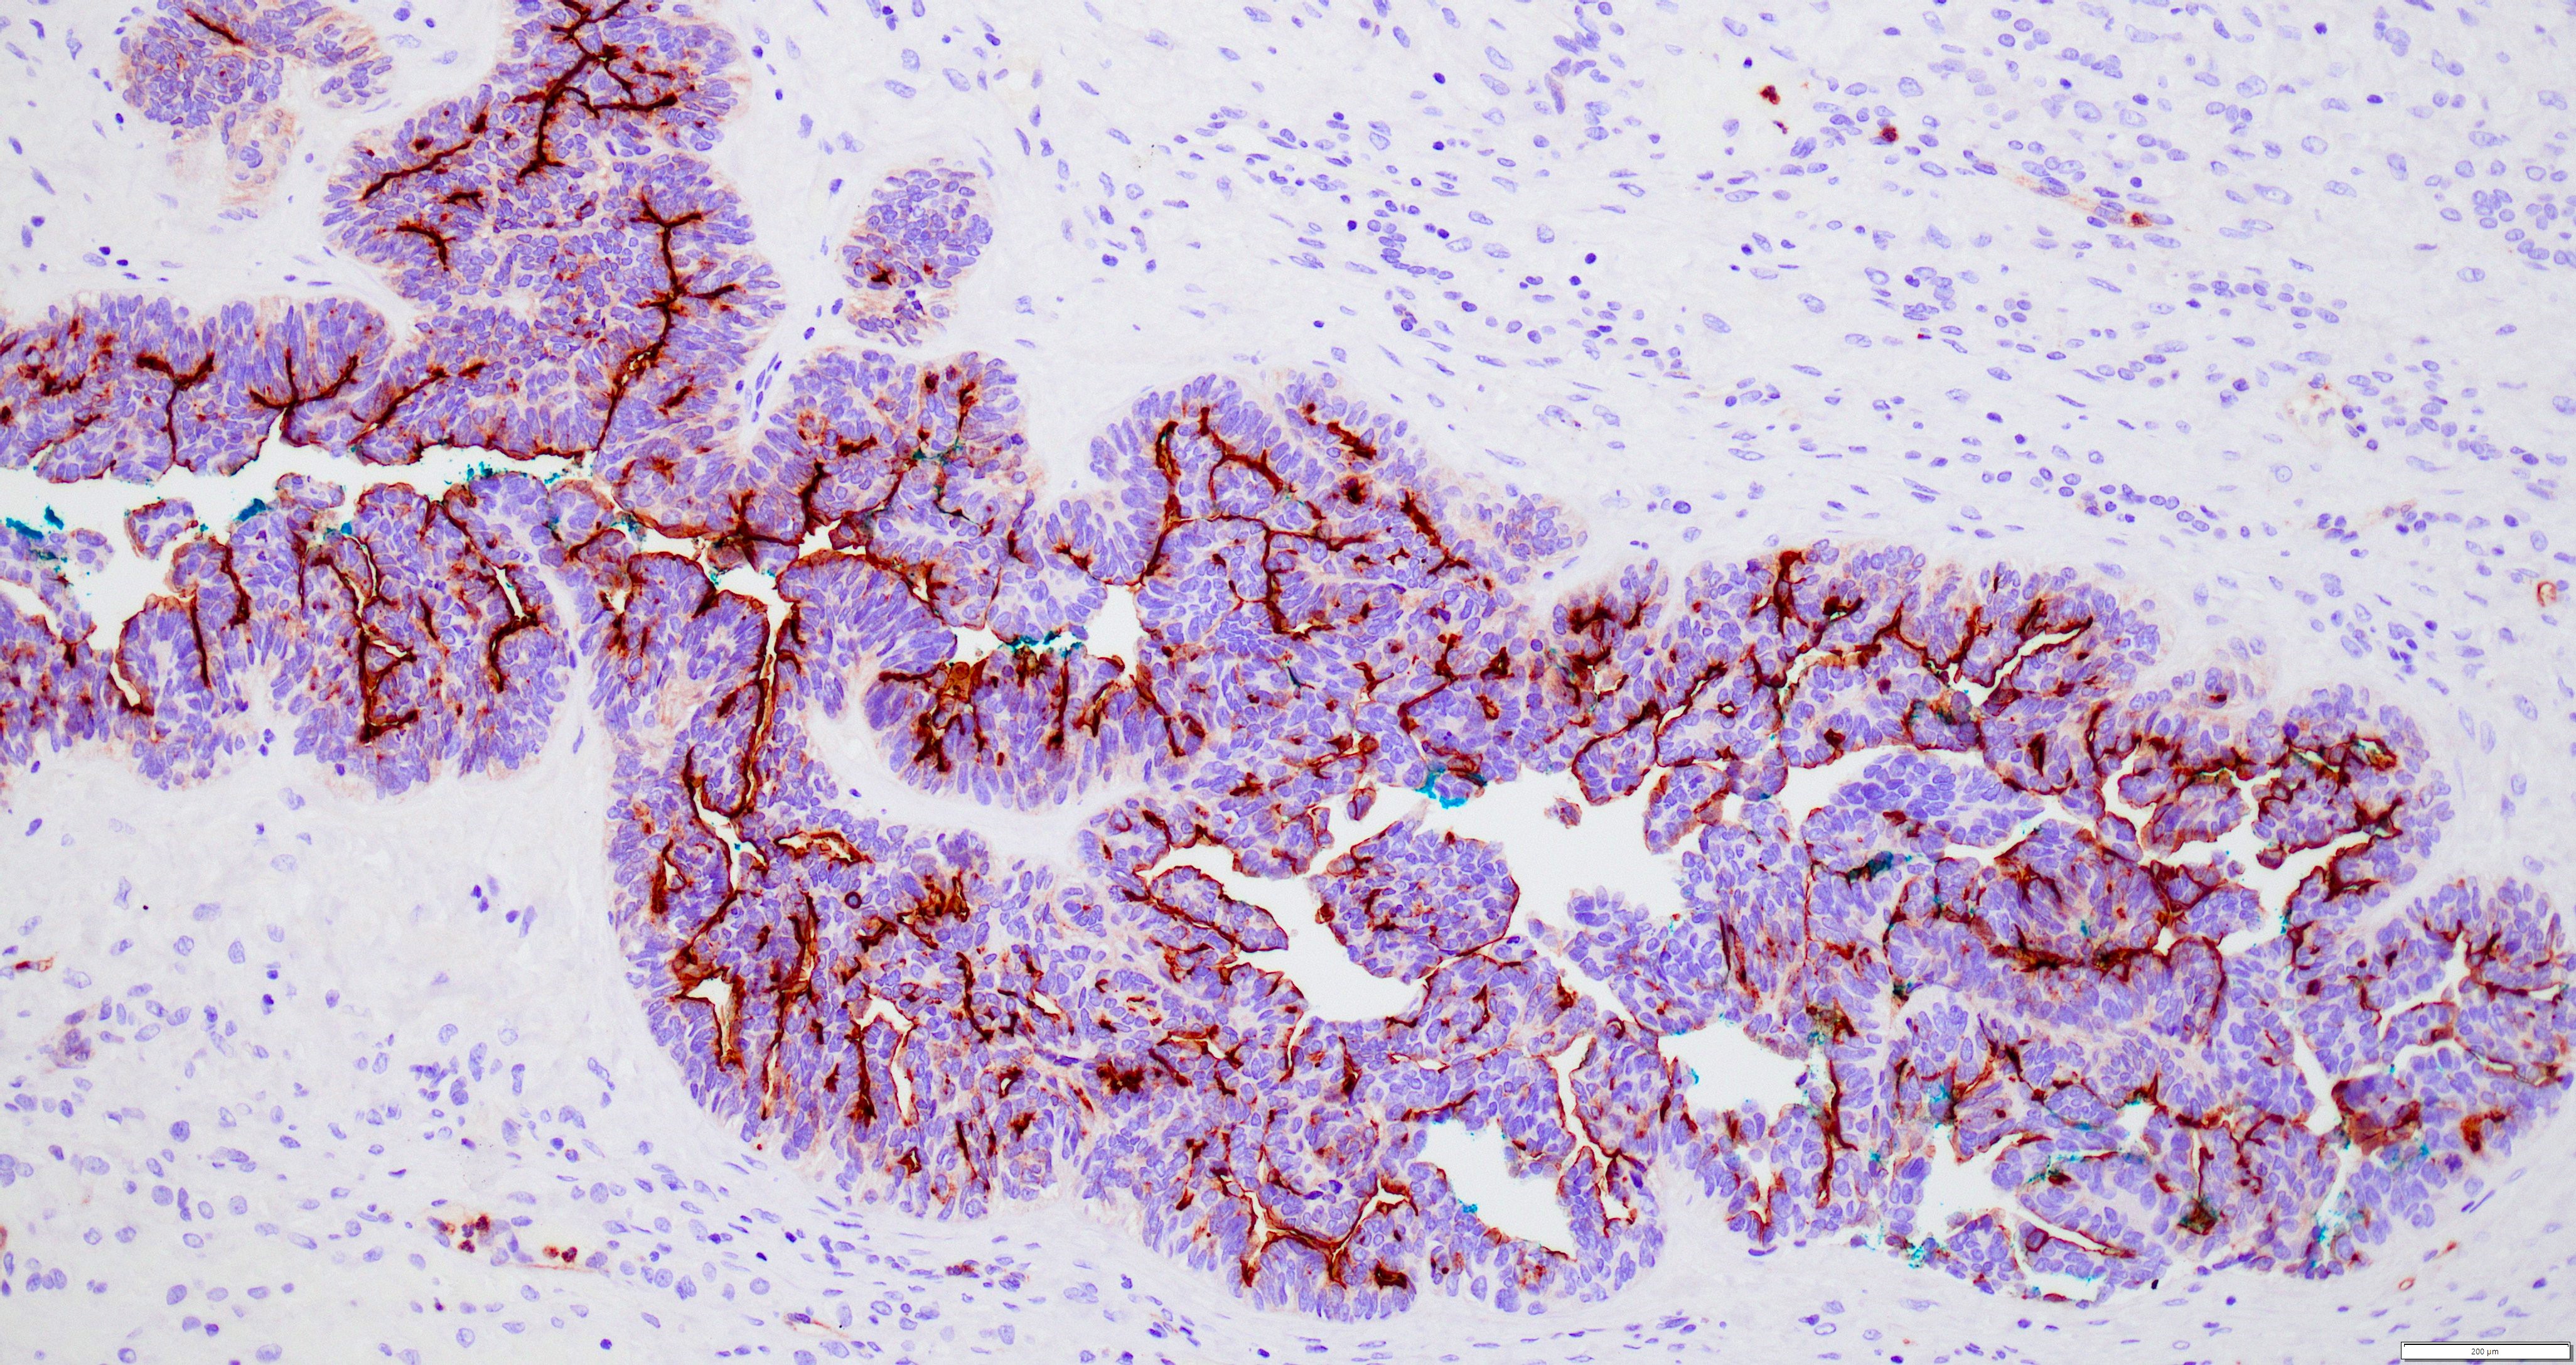

Microscopic (histologic) images

Contributed by Daniel Graham, M.D., Adele Wong, M.B., B.Ch., B.A.O. and Lucy Ma, M.D.

Positive stains

- PAX8: usually diffusely positive

- GATA3 and TTF1: focal or diffuse with inverse staining pattern described in several studies in the most recent WHO classification; cells positive for GATA3 are negative for TTF1 and vice versa (Am J Surg Pathol 2018;42:1596)

- CD10: focal and apical / luminal

Negative stains

- ER

- PR (more reliable negative marker than ER)